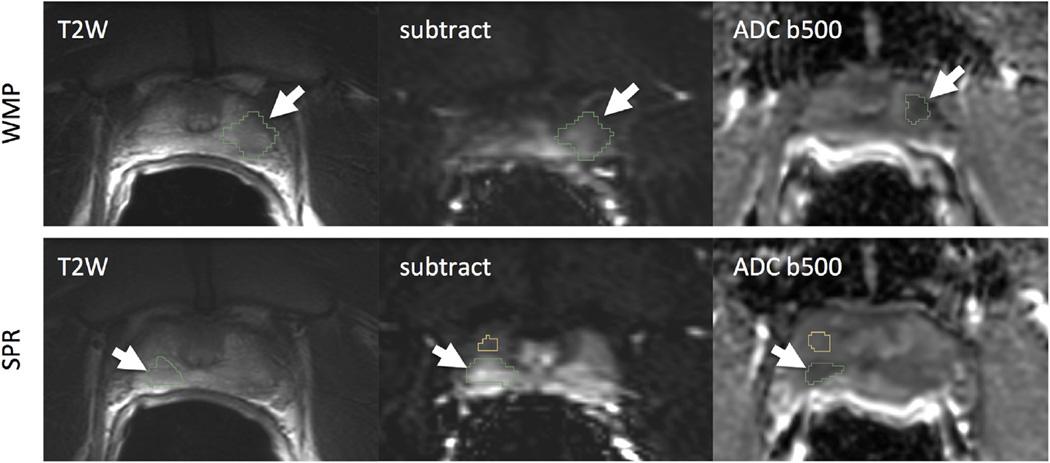

Patients (N = 30) underwent mpMRI that included diffusion-weighted imaging and dynamic contrast-enhanced (DCE) MRI at 3 T before radical prostatectomy (RP). RP specimens were processed using WM technique (WMP) and findings summarized in a standard surgical pathology report (SPR). Histology index tumor volumes (HTVs) were compared to MR tumor volumes (MRTVs) using two approaches for index lesion identification on mpMRI using annotated WMP slides as the reference (WMP) and using routine SPR as the reference. Consistency of index tumor localization, tumor volume, and mean values of the derived quantitative parameters (mean apparent diffusion coefficient [ADC], K(trans), and ve) were compared.

Index lesions from 16 of 30 patients met the selection criteria. There was WMP/SRP agreement in index tumor in 13 of 16 patients. ADC-based MRTVs were larger (P < .05) than DCE-based MRTVs. ADC MRTVs were smaller than HTV (P < .005). There was a strong correlation between HTV and MRTV (Pearson ρ > 0.8; P < .05). No significant differences were observed in the mean values of K(trans) and ADC between the WMP and SPR.

WMP correlation is superior to SPR for accurate localization of all index lesions. The use of WMP is however not required to distinguish significant differences of mean values of quantitative MRI parameters within tumor volume.

30例患者在根治性前列腺切除术(RP)前接受了3T的mpMRI检查,包括扩散加权成像和动态对比增强(DCE)MRI。RP标本采用WM技术(WMP)处理,结果汇总在标准手术病理报告(SPR)中。使用两种方法在mpMRI上识别指数病变,将组织学指数肿瘤体积(HTV)与MR肿瘤体积(MRTV)进行比较,一种是以注释的WMP切片作为参考(WMP),另一种是以常规SPR作为参考。比较指数肿瘤定位、肿瘤体积以及导出的定量参数(平均表观扩散系数[ADC]、Ktrans和ve)平均值的一致性。

30例患者中有16例的指数病变符合选择标准。16例患者中有13例的指数肿瘤存在WMP/SRP一致性。基于ADC的MRTV比基于DCE的MRTV大(P <.05)。ADC MRTV小于HTV(P <.005)。HTV与MRTV之间存在强相关性(Pearson ρ> 0.8;P <.05)。WMP和SPR之间在Ktrans和ADC的平均值上未观察到显著差异。

WMP相关性在准确识别所有指数病变方面优于SPR。然而,在区分肿瘤体积内定量MRI参数平均值的显著差异时,并不需要使用WMP。